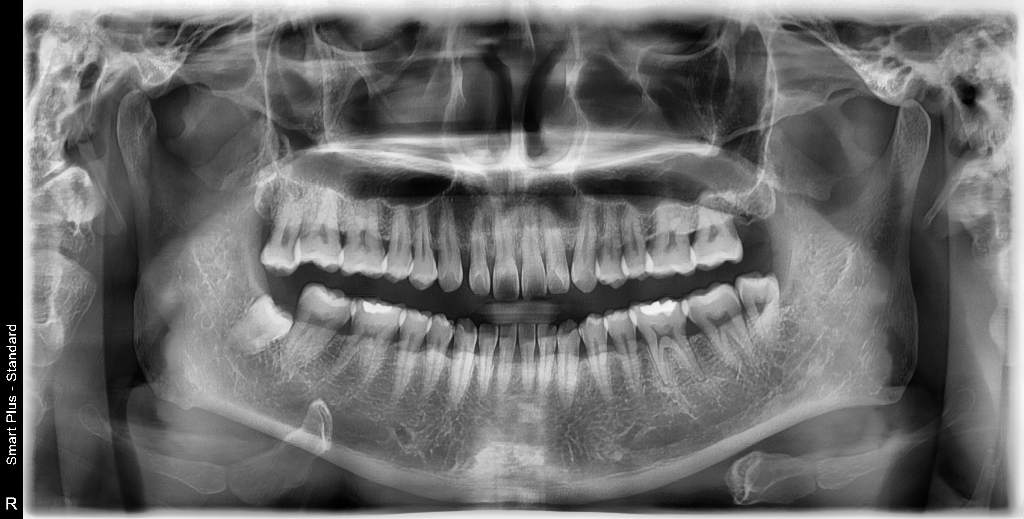

사랑니 발치해야 한다고 하는데 한개만 빼면 되는지요?

사랑니 빼야 된다고 하던데, 그냥 어렵지 않게 뺄 수있는 사랑니라고 걱정하지 말라고 하더군요. 아직 아프거나 붓거나 그런건 없습니다. 그리고 어금니 임플란트 해야한다고 하면 뼈이식까지 해야 되는지는 엑스레이만으로도 확인 할수있는지요?

사진으로만 봤을 경우에는 사랑이랑 오른쪽 위와 왼쪽 아래 하나씩 있습니다.

맞은편에 물리는 채가 없기 때문에 정출될 수 있어서 이런 사람들은 발치를 하는 것이 좋습니다 파노라마 사진상에는 임플란트를 할 만한 치아가 보이진 않습니다.

사랑니는 오른쪽 위아래 왼쪽아래 총 3개가 잇으신거 같습니다 불편하시면 발치를 하시면될것같습니다. 어금니는 아직 발치하고 임플란트 할만한 치아는 없으신거 같습니다.